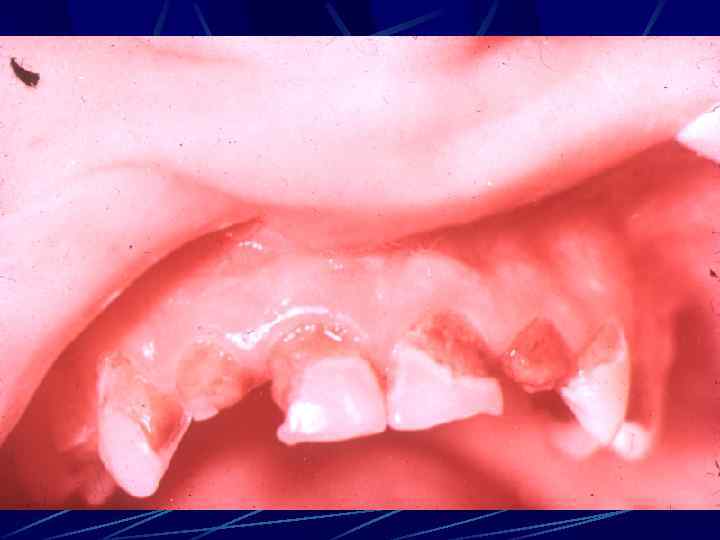

ЗАБОЛЕВАНИЯ КРАЕВОГО ПАРОДОНТА пародонтит, ассоциированный с системными заболеваниями ребенка Съемный протез ребенка 4 лет

ЗАБОЛЕВАНИЯ КРАЕВОГО ПАРОДОНТА пародонтит, ассоциированный с системными заболеваниями ребенка Съемный протез во рту у ребенка 4 лет